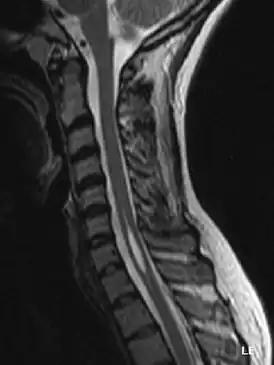

Сирингомиели́я (от др.-греч. σῦριγξ, род. п. σῦριγγος — трубка, трубчатая полость и μυελός — костный мозг, спинной мозг) — хроническое прогрессирующее заболевание нервной системы, при котором в спинном мозге образуются полости.

Т. Мilhorat в 2000 г. предложил классификацию сирингомиелии, основанную на данных МРТ и морфологических исследований. Он выделил 3 типа поражения: сообщающаяся центральноканальная сирингомиелия, несообщающаяся центральноканальная сирингомиелия, несообщающаяся экстраканальная сирингомиелия. Согласно данной классификации сообщающаяся центральноканальная сирингомиелия составляет 10—15 % всех наблюдений. Она, как правило, сочетается с аномалией Киари 2-го типа, гидроцефалией, аномалией Денди — Уокера. Несообщающаяся центральноканальная сирингомиелия составляет 75 % всех наблюдений и сочетается с аномалией Киари 1-го типа и базиллярной импрессией, а также различными причинами нарушения проходимости субарахноидальных пространств на уровне позвоночного канала (травмы и дегенеративные стенозы шейного отдела позвоночника, опухоли и т. д.). Несообщающаяся экстраканальная сирингомиелия (около 10 % наблюдений) является последствием травм и нарушений кровообращения в спинном мозге с первичным формированием кисты в зоне повреждения мозгового вещества и постепенным её распространением по длиннику спинного мозга. Классификация Т. Мilhorat удобна тем, что объединяет все виды кистозной трансформации спинного мозга, включая так называемую гидромиелию (несообщающаяся экстраканальная форма), однако патогенез и морфология кист, включённых в эту классификацию, различны.